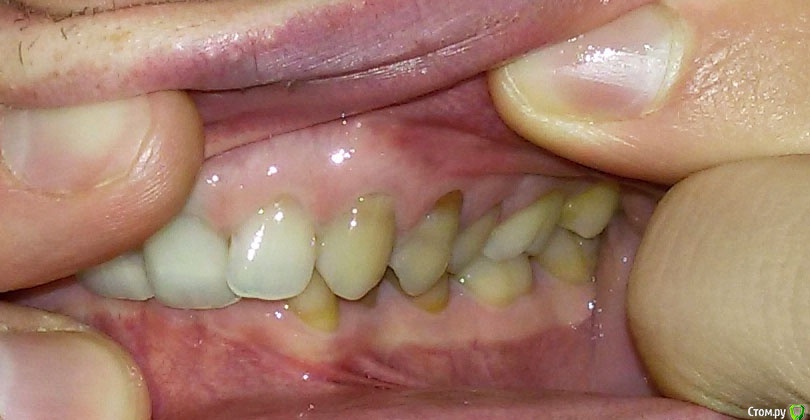

Беспокоит: Возраст 30 лет.  с 15 лет щелчки в суставе, полгода назад появилась периодическая боль - в области сустава, напряжение в жевательных мышцах, в шее  (с шеей вообще давние проблемы - не знаю, что первопричина болей), боли в затылке, голове. Глубокий прикус. Решил прикус исправлять в надежде, что боли уменьшатся.  На снимках видно, что челюсть нижняя заблокирована в заднем положении, мешают верхние резцы, головка сустава смещена

Где был: Наши местные ортодонты в Туле суставом не занимаются, единственное предложение - лечение брекетами. По их словам нижняя челюсть сама немного выдвенется когда исправим загнутые внутрь резцы вч, а выдвигать аппаратом Гербста не имеет смысла в моем возрасте - все вернется назад. Один ортодонт правда предложил тяги - но их результативность под вопросом

Был в Москве в институте на вучетича - там предложили брекеты+гербста.